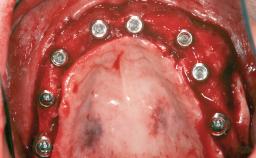

# of Implants 8

Type of Implants Reduced-Diameter|Two-Piece

Bone Augmentation Horizontal|Sinus Floor Elevation|Staged|Vertical

Augmentation Materials Autogenous chips|Autogenous block(s)

Defining Characteristics Fully edentulous upper jaw to be rehabilitated with four or more implants

Modality Fixed hybrid bridge on 5+ implants